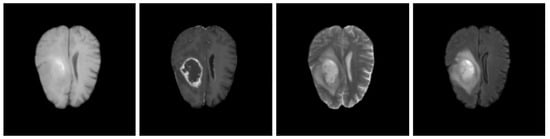

7.1. Visual Error Analysis

7.2. Error Causes